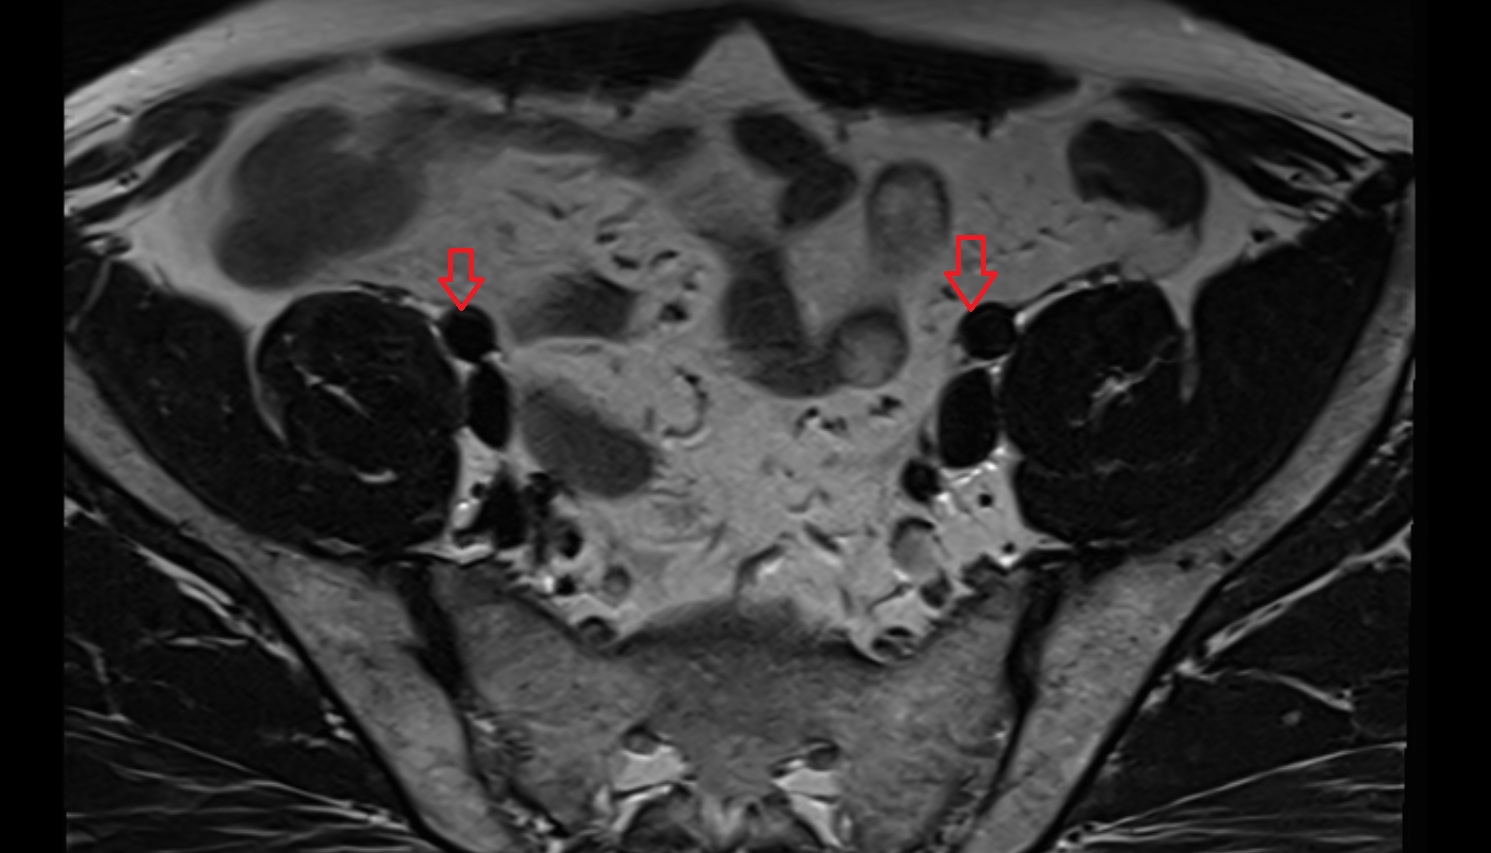

- External iliac artery

- Internal iliac artery

- External iliac vein

- Internal iliac vein

- Common iliac vein

- common iliac artery